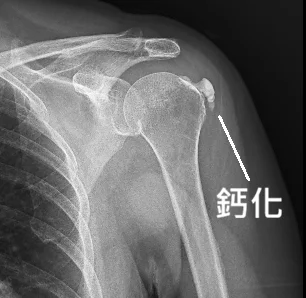

當超音波探頭滑過她的肩膀,螢幕上的影像立刻揭露了真相——哪裡是什麼嚴重的撕裂傷?在旋轉肌腱裡,赫然卡著一顆巨大的鈣化點!隨後安排的 X 光檢查,更是鐵證如山:一顆輪廓清晰、密度極高的結石,死死地卡在肩膀關節處。

謎底揭曉:這就是典型的「鈣化性肌腱炎」。

雖然因為肩膀擺位的角度略有不同,造成鈣化點在影像上的位置往下移動,但可以清楚看到鈣化明顯變小了!更重要的是,鈣化點的顏色沒這麼白了。

在 X 光影像學上,「越白代表越硬」。顏色變淡,意味著鈣化結構已經變得鬆散、軟化。接下來,只需要搭配復健運動,促進肩部的血液循環,剩下的殘餘鈣化就會隨著時間慢慢被身體「運走」。